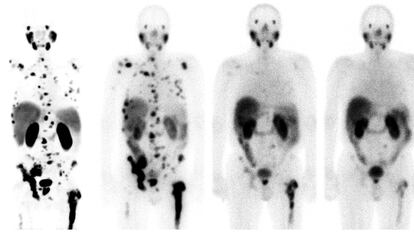

The medical treatment, which combines therapy and diagnostics, has given terminal prostate cancer patients a 35% increased survival time in trials